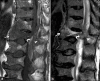

Musculoskeletal disorders are among the most common problems affecting the elderly. The resulting loss of mobility and physical independence can be particularly devastating in this population. The aim of this article is to present some of the most frequent musculoskeletal disorders of the elderly, such as fractures, osteoporosis, osteoarthritis, microcrystal disorders, infections, and tumors.